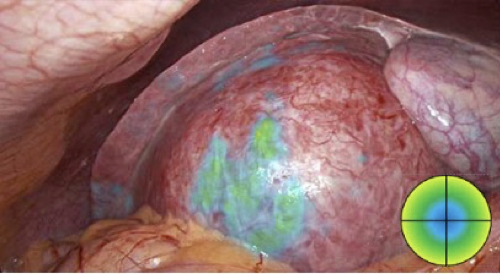

ICG/NIR fluorescence surgical imaging is one of the most valuable technologies in minimally invasive procedures, especially during intraoperative visualization of visceral perfusion, biliary structures, or lymph node mapping.

VEQTRON™ Imaging System offers four different display modes.